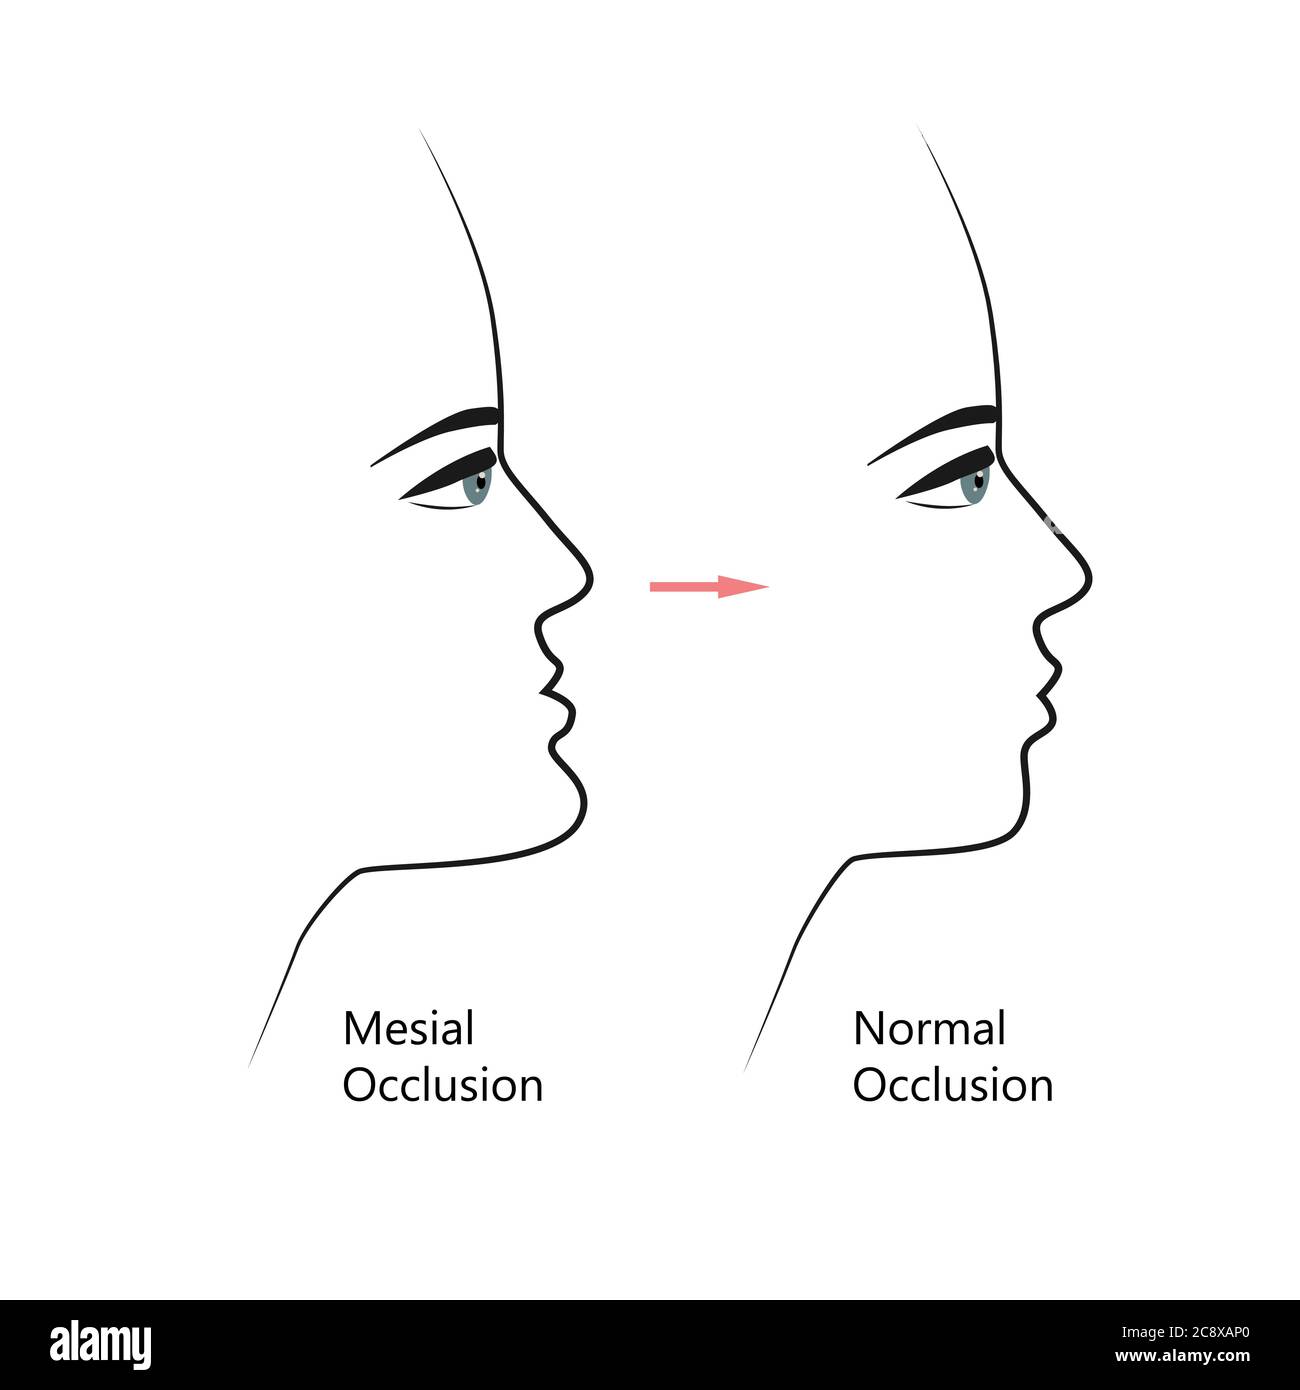

Profil de morsure mésiale avant et après un traitement orthodontique. Humain présentant une malocclusion, mâchoire inférieure étendue vers l'avant, correction des morsures par les accolades. Vecteur Illustration de Vecteurhttps://www.alamyimages.fr/image-license-details/?v=1https://www.alamyimages.fr/profil-de-morsure-mesiale-avant-et-apres-un-traitement-orthodontique-humain-presentant-une-malocclusion-machoire-inferieure-etendue-vers-l-avant-correction-des-morsures-par-les-accolades-vecteur-image366914184.html

Profil de morsure mésiale avant et après un traitement orthodontique. Humain présentant une malocclusion, mâchoire inférieure étendue vers l'avant, correction des morsures par les accolades. Vecteur Illustration de Vecteurhttps://www.alamyimages.fr/image-license-details/?v=1https://www.alamyimages.fr/profil-de-morsure-mesiale-avant-et-apres-un-traitement-orthodontique-humain-presentant-une-malocclusion-machoire-inferieure-etendue-vers-l-avant-correction-des-morsures-par-les-accolades-vecteur-image366914184.htmlRF2C8XAP0–Profil de morsure mésiale avant et après un traitement orthodontique. Humain présentant une malocclusion, mâchoire inférieure étendue vers l'avant, correction des morsures par les accolades. Vecteur